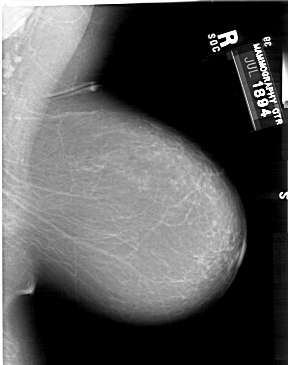

A_1498_1.RIGHT_MLO

RIGHT_CC LINES 6151 PIXELS_PER_LINE 4666 BITS_PER_PIXEL 12 RESOLUTION 43.5 NON_OVERLAY

RIGHT_MLO LINES 6556 PIXELS_PER_LINE 5176 BITS_PER_PIXEL 12 RESOLUTION 43.5 NON_OVERLAY